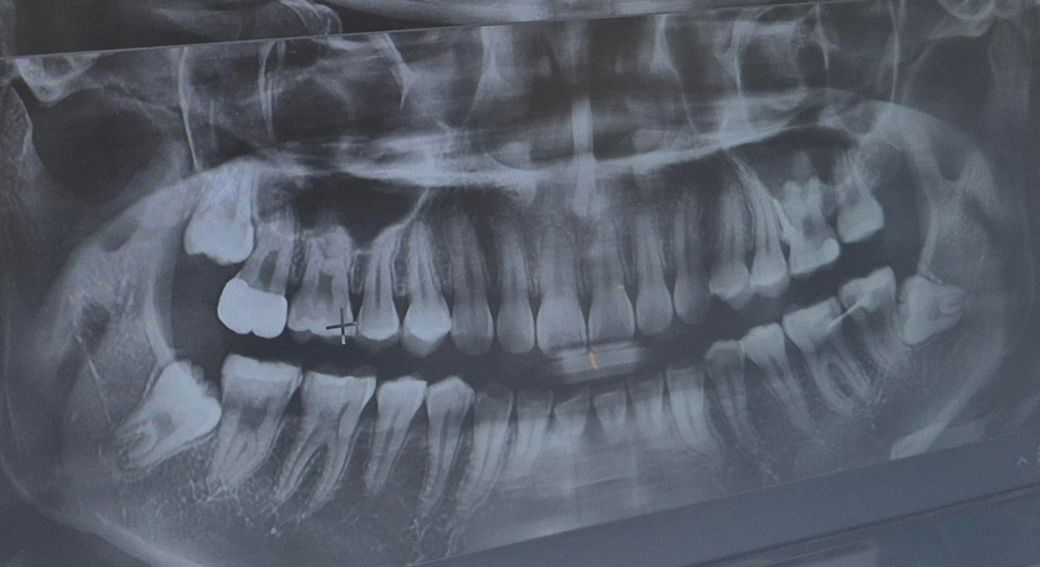

이것 때문에 치과에서 물어봤는데 큰 이상 없다고 해서요 육안으로 또는 엑스레이상으로 문제 있는 게 있을까요? 5개월 전에도 이런 증상 있었고 그때 찍은 거에요

해당 치아 자체에는 그다지 문제가 보이지는 않아서 사랑니로 인한 통증일 확률도 있겠습니다.

육안상으로나 엑스레이 상으로 크게 문제가 잇어 보이진 않습니다. 치아 표면에 교모가 되서 시리다면 추후에 신경치료를 하셔야될수도 있습니다.

오른쪽 밑 맨 뒤 어금니가 문지르면 아파요. -> 사랑니가 영향을 줬을 가능성이 있습니다. 다른 치과도 가보세요